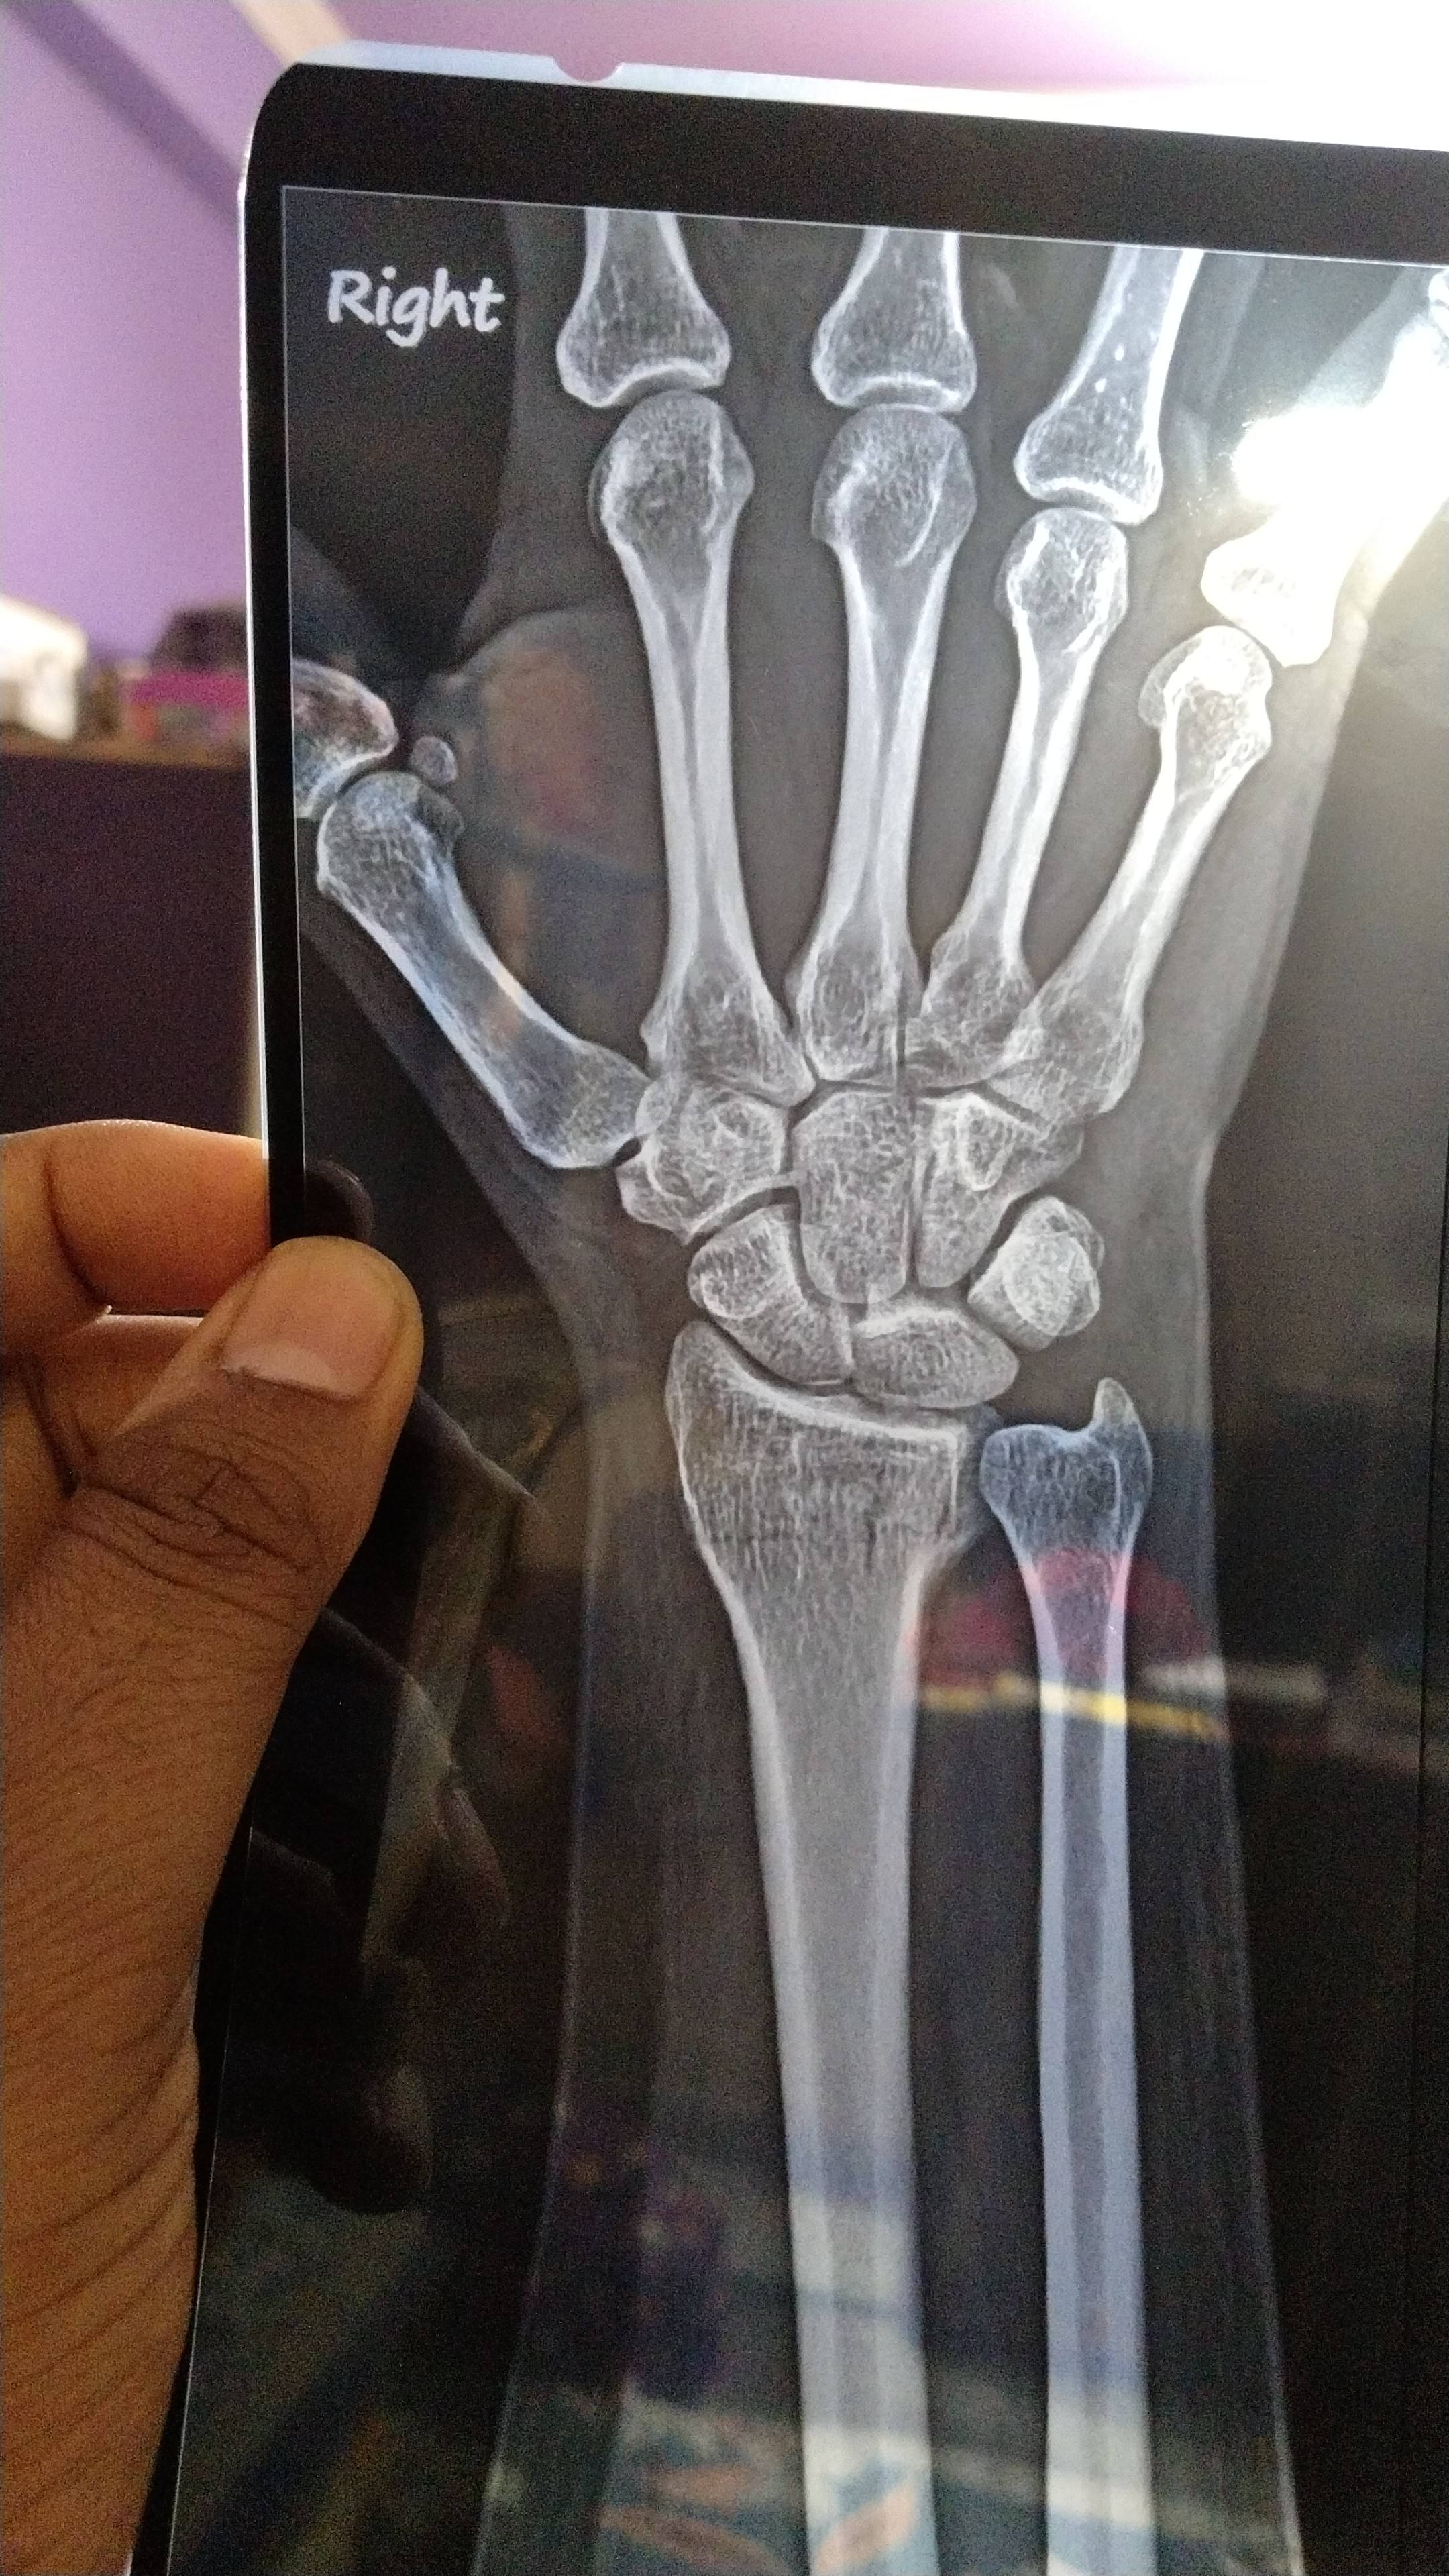

What is opinion about this fracture